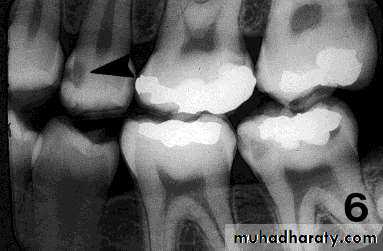

PIT & FISSURE CARIES

Incipient occlusal lesions:Not very effective.

Caries starts on the walls

of the pits & fissures and

tends to spread

perpendicular to the DEJ

Only detectable change is

a fine gray shadow at the

DEJ.

Moderate occlusal lesions:

Moderate occlusal lesions: First to induce specific changes

helping in a definitive diagnosis

Broad based, thin radiolucent

zone in dentin with minimal or

no changes in enamel

Presence of a band of increased

opacity between the lesion and

the pulp chamber due to

calcification within primary

dentin

This feature is not seen in

buccal caries

Severe occlusal lesions:

Readily observed bothclinically and

radiographically

Appear as large cavities in

the crowns of the teeth

However pulp exposure

cannot be determined

Incipient occlusal lesions

Moderate occlusal lesionsSevere occlusal lesions

Advanced proximal lesions

Incipient proximal lesionsModerate proximal lesions